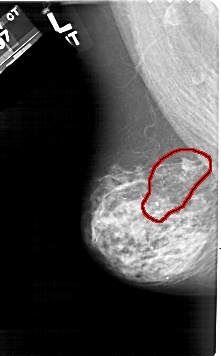

A_1510_1.LEFT_MLO

LEFT_MLO LINES 5326 PIXELS_PER_LINE 3301 BITS_PER_PIXEL 12 RESOLUTION 43.5 OVERLAY

FILE: A_1510_1.LEFT_MLO.OVERLAY

TOTAL_ABNORMALITIES 1

ABNORMALITY 1

LESION_TYPE CALCIFICATION TYPE PLEOMORPHIC DISTRIBUTION REGIONAL

LESION_TYPE MASS SHAPE IRREGULAR MARGINS SPICULATED

ASSESSMENT 5

SUBTLETY 5

PATHOLOGY MALIGNANT

TOTAL_OUTLINES 1

BOUNDARY